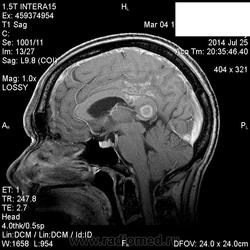

Мама приятельницы.Нарушение походки в течение 2-3 месяцев.

DDs: рассеянный склероз, токсоплазмоз, mts.

Рассеянный склероз вряд ли. Я бы добавила лимфому и глиобластому.

Думается больше о глиобластоме в форме бабочки. Из книги "Диагностическая нейрорадиология". Корниенко, Пронин.

На РС точно не похоже. Токсоплазмоз - навряд ли, т.к. "мама приятельницы", а это чаще всего бывает у ВИЧ-инфицированных.

+1 к глиобластоме.

Да, больше данных за опухоль.

Сегодня узнала: нейрохирурги за лимфому.Сделали КТ и подтвердили .